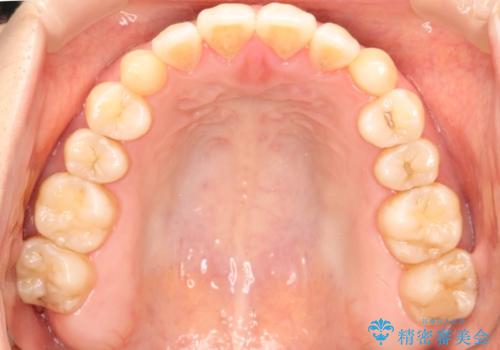

初診時の歯並びの状態としては、上下ともに前歯部に限局した軽度ののがたつき(叢生)がある状態でした。

主に歯列弓の拡大とディスキング(歯と歯の間に隙間を作る処置)を行い叢生を改善しました。

見た目、嚙み合わせ及び、治療期間や施術内容に大変ご満足いただきました。